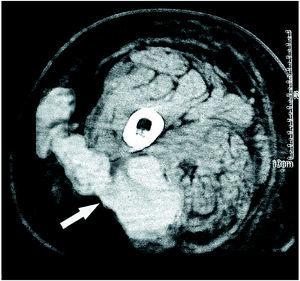

Una mujer de 80 años con factores de riesgo cardiovascular y accidentes isquémicos transitorios repetidos y que recibía tratamiento con acenocumarol y enalapril sufrió un atropello. La paciente presentaba inestabilidad hemodinámica marcada, objetivándose un hematoma de gran volumen en el muslo derecho. Precisó estabilización con cristaloides, concentrados de hematíes y plasma junto con vitamina K con normalización del valor de INR tras 24 h, con posterior aparición de ampollas cutáneas (fig. 1) y valores de presión intracompartimental siempre menores de 30 mmHg, por lo que se decidió actitud conservadora. Se realizó una tomografía axial computarizada que mostró un hematoma del músculo glúteo superior que se extendía al compartimento posterior del muslo y al tejido subcutáneo (fig. 2, flecha). La paciente evolucionó sin complicaciones.

Figura 2.